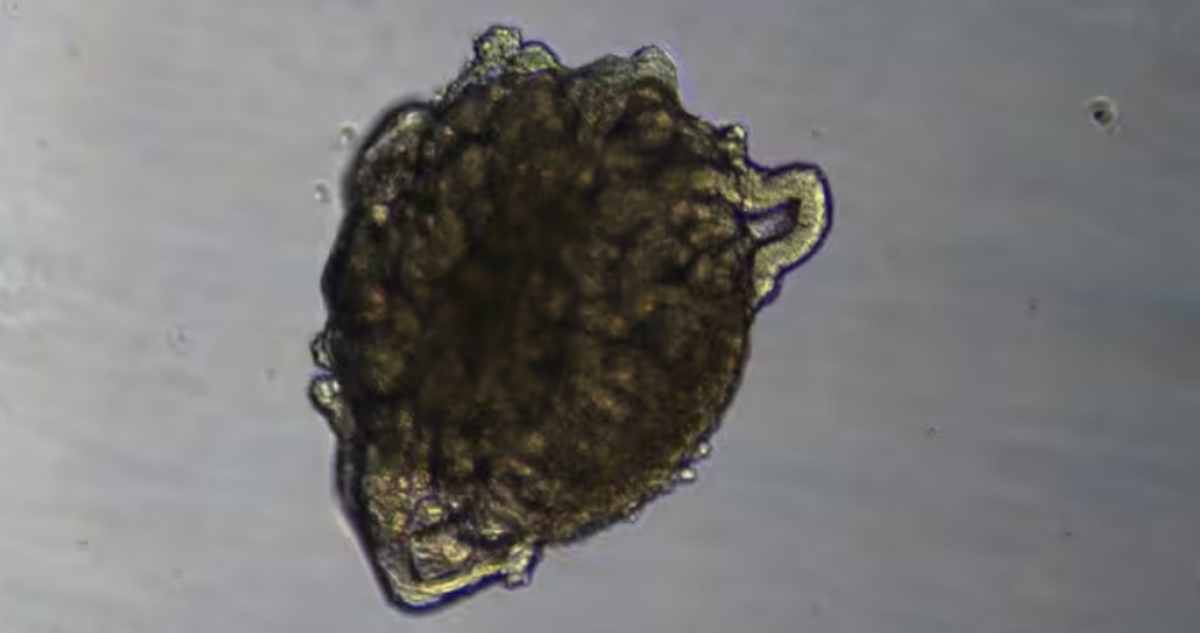

Actualmente, las pruebas de detección sistemática sólo se recomiendan para cuatro tipos de cáncer, lo que significa que aproximadamente el 70 por ciento de los nuevos casos se detectan únicamente después de la aparición de los síntomas, a menudo en una fase avanzada, cuando las tasas de supervivencia son menores. Las pruebas de detección precoz de múltiples tipos de cáncer ofrecen un enfoque revolucionario al detectar varios tipos de cáncer simultáneamente a partir de una sola muestra de sangre.